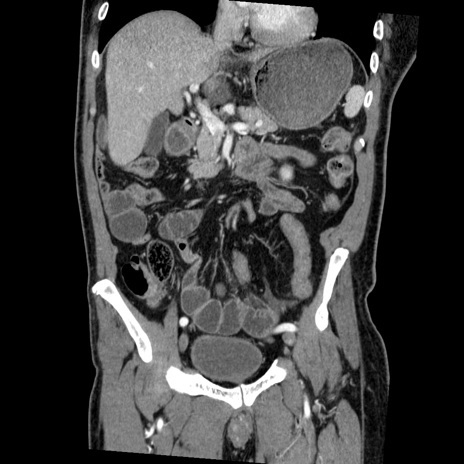

症例22(冠状断像)

【症例】50歳代男性

【主訴】腹痛

【現病歴】AVMからの被殻出血のため回復期リハ病棟入院中。 本日午後3時頃急に下腹部痛が出現した。

【既往歴】AVM、被殻出血、虫垂炎、高血圧

【身体所見】意識晴明、左半身不全麻痺、会話の理解は良好、36.5°C、腹部:膨隆、全体に板状硬、下腹部正中に圧痛点あり、反跳痛-、筋性防御不明、右下腹部にope scar

【データ】WBC 9400、CRP 0.06